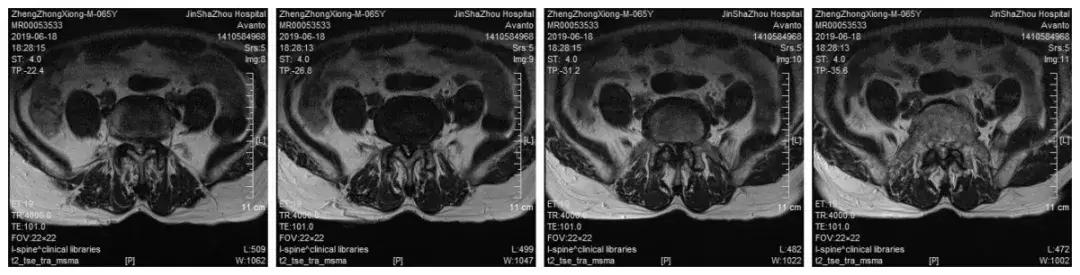

影像学检查